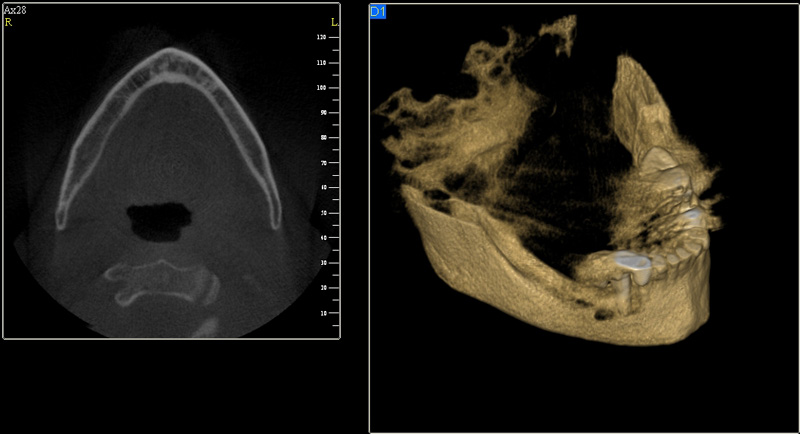

Tento výkon se nazývá sinus lift - aplikace kostního granulátu do čelistní dutiny

Při ztrátě molárů a premolárů v horní čelisti a jejich náhradě implantáty se často setkáváme s nedostatečnou vertikální nabídkou kosti pod čelistní dutinou, často doprovázenou i nedostatečnou horizontální nabídkou a sníženou kvalitou kosti

(v oblasti 2. premoláru v 50%, v oblasti moláru až v 80% případů nedostatečná kostní nabídka)

Od roku 1985 je tento problém řešen augmentační operací nazývanou sinus lift.

Jedná se o vyzvednutí membrány, která čelistní dutinu vystýlá, pod vyzvednutou membránou vznikne kapsa, kam se umístí augmentační materiál, do kterého se zavedou implantáty.

Vhojení implantátů se při této operaci prodlužuje na 6-12 měsíců.